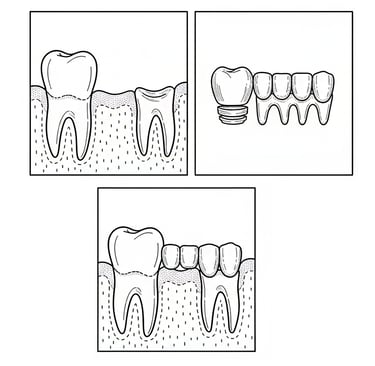

Το οδοντικό εμφύτευμα είναι μια μικρή βίδα (συνήθως από τιτάνιο ή ζιρκόνιο) που τοποθετείται στο οστό της γνάθου στη θέση ενός χαμένου δοντιού. Λειτουργεί σαν τεχνητή ρίζα.

Προσθετική εργασία

Η προσθετική εργασία περιλαμβάνει αποσπώμενες οδοντικές αποκαταστάσεις που αντικαθιστούν τα χαμένα δόντια και το μαλακό ιστό. Προσφέρει βελτίωση στην αισθητική, την ομιλία και τη μάσηση, είναι οικονομικότερη και εύκολη στην επισκευή.